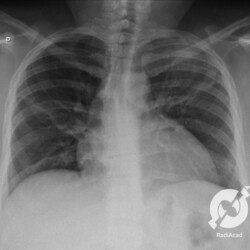

Os agentes etiológicos infecciosos são variados (bactérias, vírus, fungos, parasitas…), mas o que ocorre nos pulmões durante uma infecção por qualquer tipo de agente é a substituição do ar alveolar por secreção (pus, muco, eventualmente sangue ou necrose…) e com isso a manifestação radiográfica vai ser a mesma já que todas estas secreções apresentam a mesma densidade radiográfica: partes moles.

E o nome dado a esta alteração radiográfica que corresponde à substituição do ar alveolar por líquido é a consolidação alveolar.

Uma consolidação alveolar é, por definição, uma opacidade (imagem densa, branquinha) homogênea ou às vezes heterogênea (pela presença de calcificações ou cavidades), de limites mal definidos, exceto quando toca a pleura da parede ou das cissuras pulmonares. É um termo usado tanto em radiografia, como em tomografia computadorizada. Na tomografia, um outro termo é usado: vidro fosco, que é uma opacidade (branquinha mas não tanto como a consolidação), que borra o pulmão mas deixa ver os vasos de permeio (igual bigode de adolescente: dá pra ver todo o fundo).

Nós vamos mostrar aqui um pequeno apanhado de pneumonias de variados agentes, em diversos segmentos e lobos pulmonares, com extensões variadas. O objetivo é identificar o padrão radiológico de consolidação alveolar e não determinar o agente infeccioso, isso vai ser assunto para mais adiante. Aliás já antecipo que é fundamental saber localizar a lesão, porque alguns destes bichos gostam de determinados segmentos, alguns tumores também têm as suas preferências, então localização é fundamental. Se localização não fosse importante, um apartamento na beira do mar sairia o mesmo preço de um apartamento de frente pra BR-101, concordam?

Seguem alguns dos nossos casos de pneumonia para vocês treinarem os olhos e não se apavorarem nos plantões.